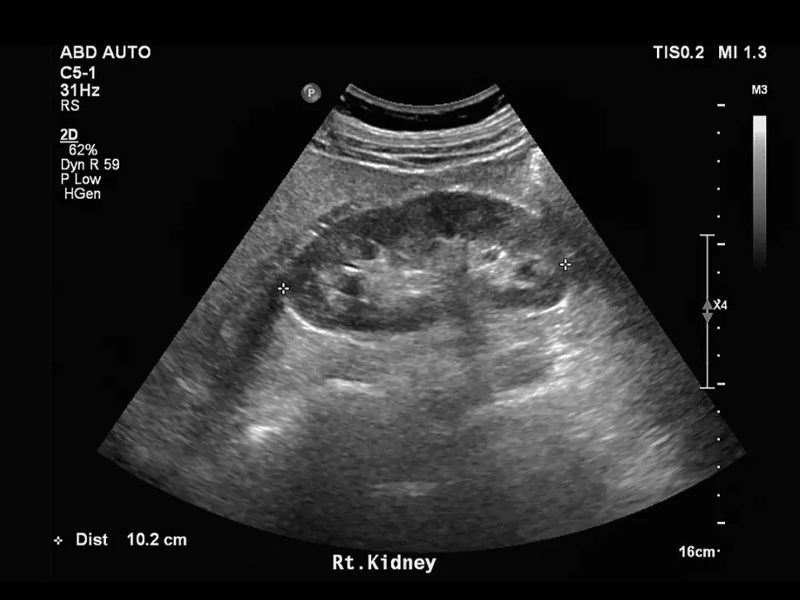

Hình ảnh siêu âm sỏi thận

Thông qua hình ảnh của siêu âm thì bác sĩ biết được chính xác kích thước sỏi thận là bao nhiêu? Hình dạng sỏi có nhẵn hay nhiều cạnh, dạng chùm hay từng viên riêng rẻ.

Mặt khác, siêu âm giúp phát hiện được sỏi thận có đang dịch chuyển xuống các vị trí khác hay không. Tình trạng thận có bị viêm, sưng hay đường niệu quản và bàng quang có gặp bất thường không.

Ngoài ra, qua hình ảnh siêu âm ghi nhận sẽ giúp bác sĩ chẩn đoán được chính xác các biến chứng của sỏi thận gây nên. Từ đó, bệnh nhân sẽ được điều trị bằng các phác đồ tốt nhất để nhanh hết bệnh.